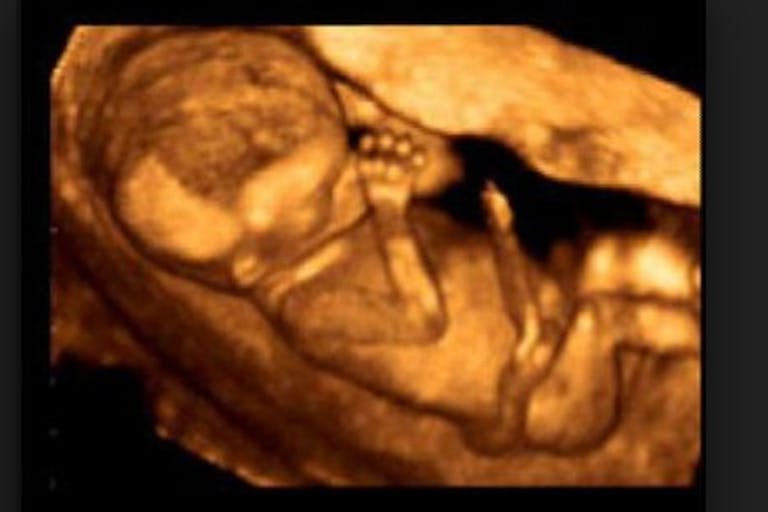

What’s so striking about the statement is The Guardian’s use of the phrase “unborn babies.” It seems that the editors of The Guardian know that the being carried in a woman’s womb is a baby – at least when that child is wanted.

So we see that in both the guest articles it chooses to run and in the way it covers the news, The Guardian is overwhelmingly biased in favor of abortion. Yet its editors admitted that children in the womb are “unborn babies”; they just admitted it in an article that has nothing to do with abortion.

This is just more evidence that even those in favor of abortion know that it kills “unborn babies.”